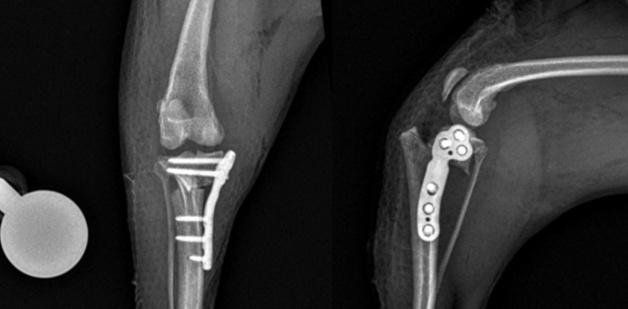

산책 중 다리 들고 걷던 강아지, 고관절 보존 수술 받고 회복

강아지가 산책 중 갑자기 절뚝거리거나 한쪽 다리를 들고 걷는 증상은 단순한 근육 문제를 넘어 관절 손상의 신호일 수 있다. 실제 고관절 탈구로 동물병원에 내원한 반려견이 관절 보존 수술을 통해 기능 회복에 성공한 사례가 공개됐다.본동물의료센터는 최근 고관절 탈구로 내원한 7년령 푸들 환자에게 인대재건술(Toggle pin)을 적용해 고관절을 보존하는 수술적 치료를 시행했다고 밝혔다.14일 본동물의료센터에 따르면 해당 환자(환견)는 산책 도중 갑